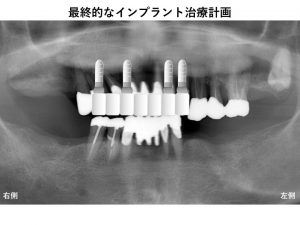

そこで最終的なインプラント治療プランは以下となりました。

奥歯にインプラント治療を行わないわけですから

前歯への負担は大きくなります。

しかし最初のベストプランではあまりにも治療費が高額になってしまい、

現実的には行うことができないのです。